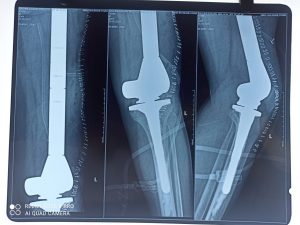

After careful surgery, whole of the tumor was excised in toto and total femur megaprosthesis was implanted by Dr Tripathy and his team. The surgery took around 4 hours. Dr Aparajita Panda and her team provided anaesthesia to the team.

This was the first surgery of total femur replacement in Odisha. Post-surgery patient is fine, said Dr Tripathy. However, the patient has to receive further chemotherapy.